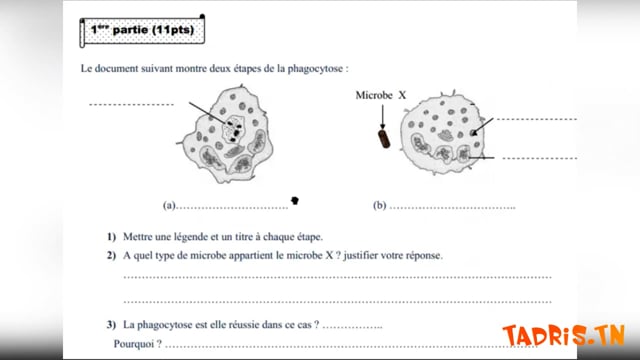

Sciences SVT